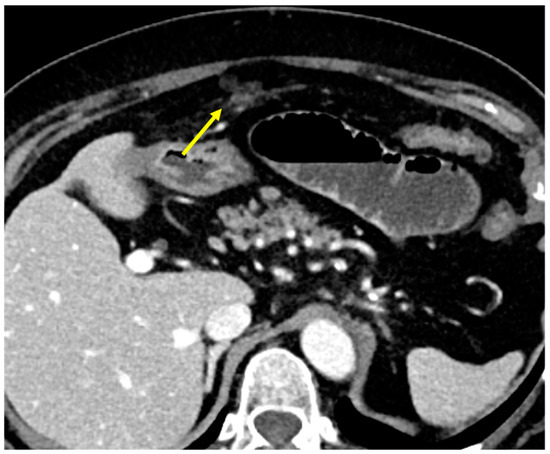

- Micro-nodular pattern: micro-nodules with a diameter ≤ 5 mm (Figure 1);